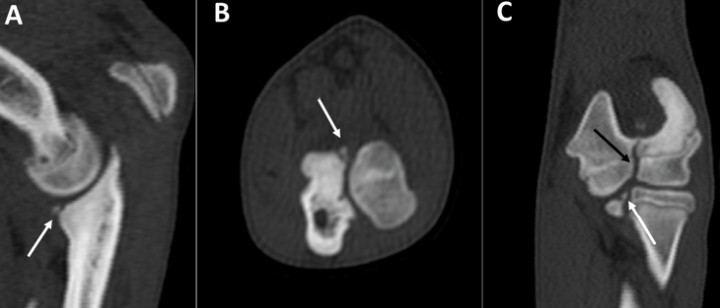

De los 66 codos estudiados 53 fueron positivos al diagnóstico de EACM en forma de: fragmentaciones (41 codos), fisuras (8 codos), esclerosis (3 codos) y osteomalacia (1 codo) (Fig. 1). La fragmentación se mostró como un único fragmento de 1,5 a 8 mm unido o separado a la apófisis coronoides medial en casi todos los casos, salvo en 3 codos donde aparecieron 2-4 fragmentos. En todos los casos de fragmentación clara los signos aparecían en los tres planos de corte: transversal, dorsal y sagital. Estos planos de corte permitieron diferenciar, además de la fragmentación, signos de degeneración articular sutiles, no siempre apreciados en las radiografías. Las fisuras se diagnosticaron siempre que fuesen visibles en al menos dos de los tres planos de corte (transversal y dorsal, o transversal y sagital). Los casos de esclerosis y ostemalacia de la apófisis resultan dudosos en la TC y solo se incluyeron tras su confirmación artroscópica. Otras lesiones asociadas fueron la OC (6 codos) (Fig. 2), la NUPA (3 codos) (Fig. 3) o la IA (Fig. 4). Como patologías concomitantes se detectaron: osificación incompleta del cóndilo humeral (1 codo) (Fig. 5), fragmentos avulsionados, (2 codos) (Fig. 6), y remodelación en el epicóndilo lateral del húmero (1 codo) (Fig. 7), detectándose como hallazgo la presencia de sesamoideos en el músculo supinador (4 codos). La gran mayoría de los casos (58 codos) presentaban artrosis de diverso grado (Tabla 3).

<p>Labrador macho de 8 meses con cojera bilateral. Codo derecho. Planos transversal (<strong>A</strong>), dorsal (<strong>B</strong>) y sagital (<strong>C</strong>). Se indica la fragmentación de la apófisis coronoides medial (flechas blancas). La escotadura radial aparece muy irregular (flecha negra) y presenta esclerosis de la escotadura subtroclear del cúbito (flecha roja). Existe una buena congruencia articular.</p>

Labrador macho de 8 meses con cojera bilateral. Codo derecho. Planos transversal (A), dorsal (B) y sagital (C). Se indica la fragmentación de la apófisis coronoides medial (flechas blancas). La escotadura radial aparece muy irregular (flecha negra) y presenta esclerosis de la escotadura subtroclear del cúbito (flecha roja). Existe una buena congruencia articular.